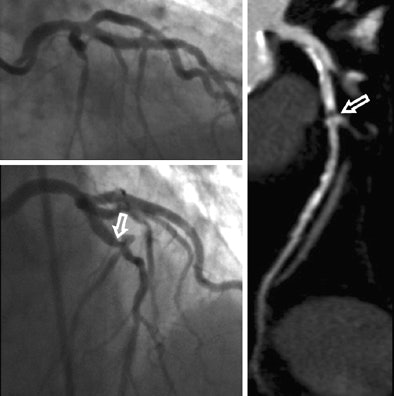

"We had two cardiologists interpret those catheter angiographies blinded, then based on result of coronary CT angiography, we alerted those same interpreters to areas that looked funny on CTA -- and we asked them to have a second look to see if there was something they had missed. And that was indeed so in a number of cases," Schoepf said.

A total of 113 patients underwent both coronary CTA and invasive angiography, and the researchers assessed the per-segment and per-patient accuracy of coronary CTA compared with initial angiography interpretation. Angiographers were then unblinded to the coronary CTA results to re-evaluate angiography with knowledge of the coronary CTA findings -- the enhanced reference standard.

Coronary CTA found six segments and two patients with stenoses of 50% or greater that had been missed on initial angiography. The diagnostic accuracy between the tests was not significantly different (p = 0.87).

A current article in Circulation describes problems with the projection angles in catheter angiography, Schoepf said. Depending on the angle, a minor slit stenosis can appear quite significant at angiography, leading to false positives and potentially needless intervention.

"If you take vertical projection images of that it may look perfectly fine, but if you're angulated by 90°, you see a significant stenosis all of the sudden," he said.